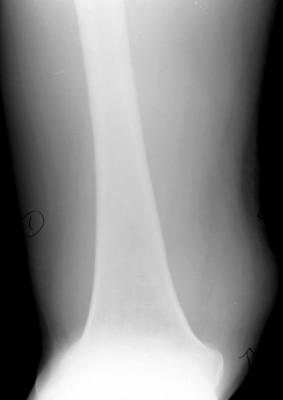

骨肉瘤:最常见的恶性骨肿瘤

临床:1、年龄:青少年(11-20岁占50%),男多于女;2、部位:以膝关节、肱骨上端多见。;;发生于干骺端。

影像学表现:1.源于骨髓腔的不规则的骨破坏和骨增生;2.骨皮质破坏,骨膜增生–葱皮样、放射状,Codman三角(袖口征)-骨膜增生被破坏形成

3.软组织肿块,其内见肿瘤骨(诊断骨肉瘤要点)。云絮状、针状、放射状、斑块状

4.不累及关节;5.病理性骨折

桡骨上段成骨型骨肉瘤:骨质增生硬化,并有骨膜反应,软组织肿块

股骨下端溶骨型骨肉瘤